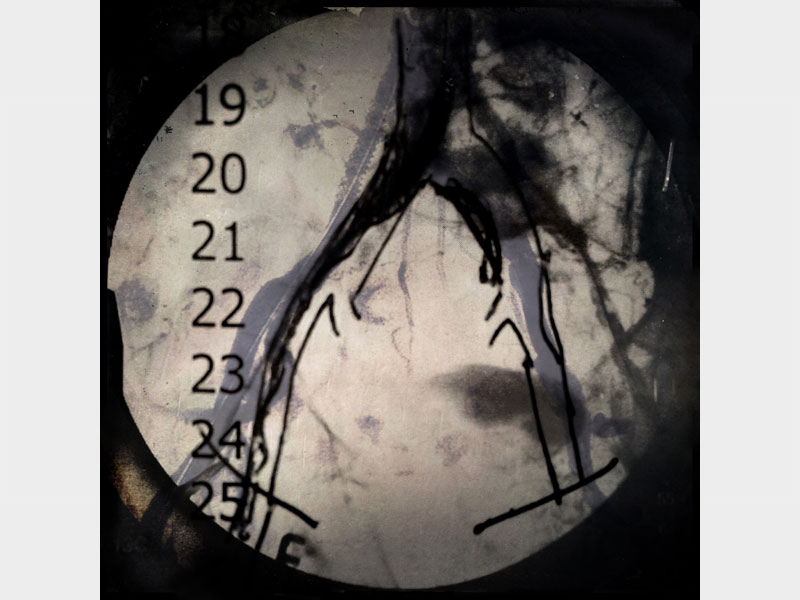

L’ospedale è un corpo fatto di tantissime vite, storie di uomini in prima linea o rimasti sempre dietro le quinte. Nelle “lastre” di Fotoscopia risplende la fulminante bellezza dei metodi diagnostici, esposta per celebrare la propulsione esplorativa dell’Arcispedale Santa Maria Nuova di Reggio Emilia e i cinquant’anni della sua sede.

Il luogo si manifesta in tutti i suoi aspetti, da creazione architettonica a struttura organizzata, da centro di ricerca a scenario di cambiamenti epocali. Nell’opera di Alessandra Calò trovano posto senza gerarchie le topografie d’archivio e gli schizzi esegetici dei dottori, gli screening mammografici e i pesci rossi della sala d’attesa. La ricerca dei materiali – condotta tra i reparti in decine di colloqui con medici, infermieri, tecnici e inservienti – ha seguito un approccio “domestico”, utile a rappresentare uno spazio dove la vita della comunità continua nei suoi ritmi quotidiani.

Catturate in prevalenza con l’ausilio dell’iphoneography ma stampate su vetro con metodi antichi, le immagini fotoscopiche di Alessandra Calò non accettano di rappresentare la realtà nei limiti della distanza digitale. Piuttosto tornano indietro nel tempo fino a recuperare il conforto del tatto, l’affabilità di una tecnica sapiente come quella del medico che comprende al tocco. In trasferta per un soggiorno speciale nella Galleria Parmeggiani, l’ospedale mostra le proprie viscere attraverso la fotografia.